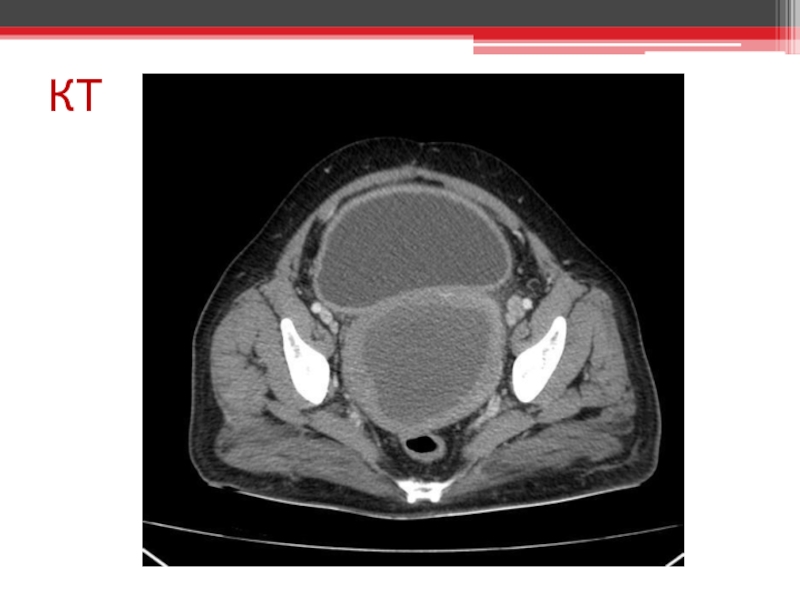

Атрезія дівочої пліви. Гематокольпос. Гематометра. Гематосальпінкс. Гострий місцевий перитоніт. Гостра затримка

сечі. Гідрокалікоз.